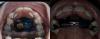

Всё просто - на год ставим аппарат Марко Росса. Прикус отличный, уздечку подрезать не надо (двое ортодонтов настаивали на этом), немного не хватает места для верхних клыков (которые ещё вообще не собираются меняться) и всё. Объяснила, почему сейчас верхние двойки криво растут и показала, как и почему всё изменится после смены клыков (то есть, здесь ничего специально не надо сейчас делать). Пару моляров полечим у своего стоматолога (они ещё, на основании КТ, тоже минимум пару лет простоят).

И по Марте меня успокоили (на втором фото проблема 😂) молочный зуб шатается, но не выпал, а коренной уже вылез. Внезапно, пока мы были на море. И вот как три недели прошло, а молочный всё не может выпасть. И это ничего страшного, если не мешает ребёнку. Можно ждать и месяц, и два, всё потом встанет на место. Но она, скорее всего, тоже кандидат на этот аппарат 😅